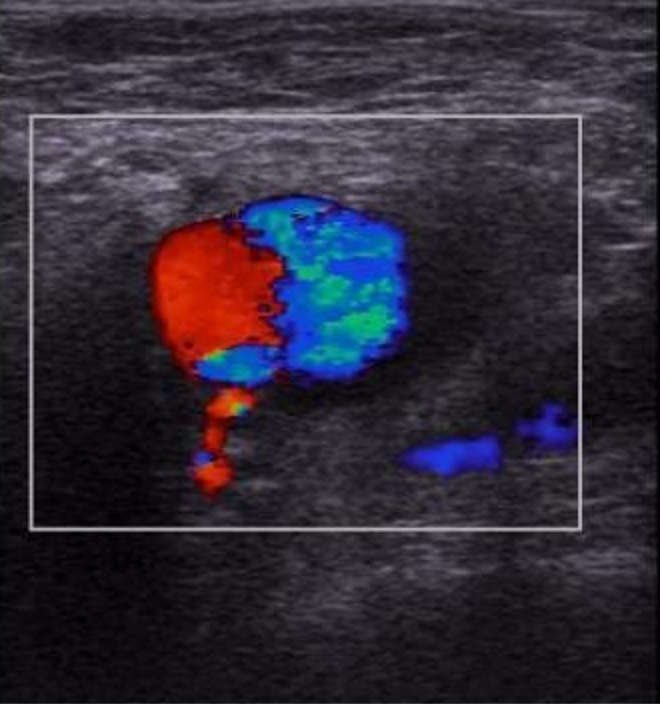

right groin US image with color doppler. What intervention did the pt likely have, diagnosis, and what is the treatment?

femoral artery pseudoaneurysm with classic “yin-yang” sign indicated to and fro flow into and out fo the pseudoaneurysm sac.

likely right femoral arterial access recently (like heart cath)

treatment = ultrasound guided thrombin injection. GOAL: introduce thrombogenic material under sonographic visualization to eleimate visible flow within the pseudoaneurysm sac